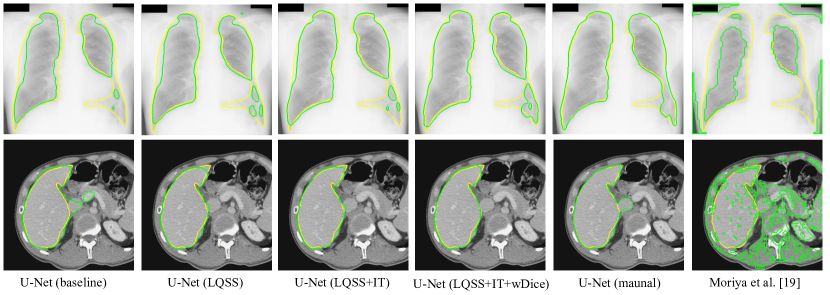

To validate our noise-robust iterative method to learn from noisy pseudo labels obtained by , we compared the following variants: 1) U-Net (baseline) that learns from the pseudo labels using a standard Dice loss without considering the existence of noise; 2) U-Net (MAE) that uses MAE loss [38] for training; 3) U-Net () that uses generalized cross entropy loss [40] for training; 4) U-Net trained with Dice loss from samples selected by our LQSS, which is referred to as U-Net (LQSS). These four methods only train the model once without iterative training, and were further compared with: 5) U-Net (LQSS + IT) that refers to U-Net (LQSS) followed by iterative training with Dice loss; and 6) U-Net (LQSS + IT + wDice) that refers to U-Net (LQSS) followed by iterative training with our noise-weighted Dice loss. For the last two variants, the round number determined by the validation set was 3 and 4 for optic disc segmentation and fetal head segmentation, respectively. The quantitative evaluation results are shown in Table 4, which shows that LQSS obtained better performance than the baseline, and using iterative training and noise-weighted Dice loss further improves the segmentation accuracy. Fig. 8 shows that our LQSS is able to reject low-quality pseudo labels with some noise, e.g., over segmentation with false positives. Note that in Fig. 8(a), the second rejected case of has a higher contrast than the first accepted case, which shows our LQSS does not tend to only select easy samples. Fig. 6 demonstrates the refinement of pseudo labels at different rounds of training stage. Fig. 9 shows the performance at different rounds of our iterative method to learn from noisy pseudo labels obtained by . It shows that the performance increased at the beginning and reached a plateau after two rounds for optic disc and three rounds for fetal head, and that noise-weighted Dice loss is better than Dice loss during the iterative training. We compared our ellipse-based shape prior with circle-based shape prior to obtain the pseudo labels, and they are denoted as U-Net (baseline) and U-Net (baseline)∘, respectively. Results in Table 4 show that modeling optic disc and fetal head as ellipses largely outperform modeling as circles.

To validate our noise-robust iterative method to learn from noisy pseudo labels obtained by our generator , we first compared the following variants: 1) U-Net (baseline) that learns from the pseudo labels using a standard Dice loss without considering the existence of noise; 2) U-Net trained with Dice loss from samples selected by our LQSS, which is referred to as U-Net (LQSS). These two methods only train the model once without iterative training, and were further compared with: 3) U-Net (LQSS + IT) that refers to U-Net (LQSS) followed by iterative training with Dice loss (five rounds); and 4) U-Net (LQSS + IT + wDice) that refers to U-Net (LQSS) followed by iterative training with our noise-weighted Dice loss (five rounds). The quantitative evaluation results are shown in Table 6. It can be observed that the LQSS obtained better performance than the baseline, and using iterative training and noise-weighted Dice loss can further improve the segmentation accuracy. As shown in Table 6, the iterative training with our noise-weighted Dice loss improved the segmentation Dice score from 0.907 to 0.926 for the lung, and from 0.908 to 0.933 for the liver, respectively. The results show that iteration process is important for learning from noisy pseudo labels. Fig. 13 demonstrates the pseudo labels refined at different rounds of training stage, and it can be observed that the quality of pseudo labels are gradually improved during the training rounds. Fig. 15 shows the performance of iterative training on the testing set. It demonstrates that the performance increased at the beginning and reached a plateau after four rounds, and also shows that noise-weighted Dice loss is better than Dice loss during the iterative training.